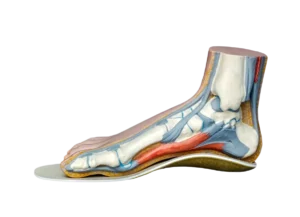

Las plantillas podológicas son, probablemente, uno de los tratamientos más conocidos dentro de la podología…...